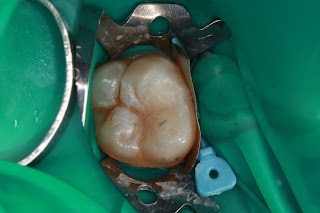

窩洞製備完成

各個角度確認無受感染的牙本質(Infected dentin)

確認靠牙齦邊緣完整的以金屬隔片/wedge/防濕帳密封